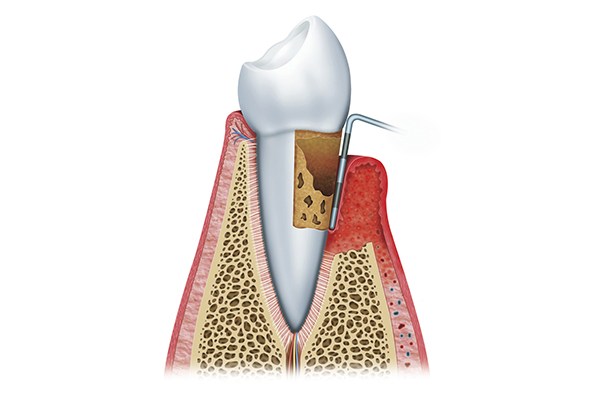

A principal causa para o aparecimento de doenças periodontais é a acumulação de placa bacteriana no sulco gengival, causando uma inflamação crónica que, se não for tratada atempadamente, pode levar a que os dentes comecem a abanar, podendo até cair.

É uma área que engloba tratamentos de rotina como as destartarizações, curetagens e alisamentos radiculares, e tratamentos mais avançados através de técnicas de microcirurgia periodontal, recobrimentos radiculares, enxertos gengivais, alongamentos coronários, regeneração óssea e gengival.